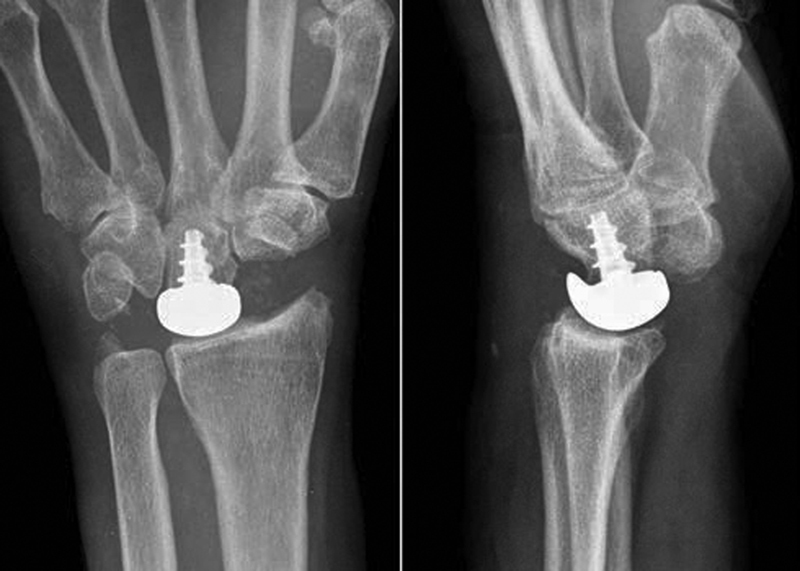

Fig. 12.

The head of the capitate is resurfaced with a modular cobalt–chrome prosthesis fixed with a titanium threaded post.